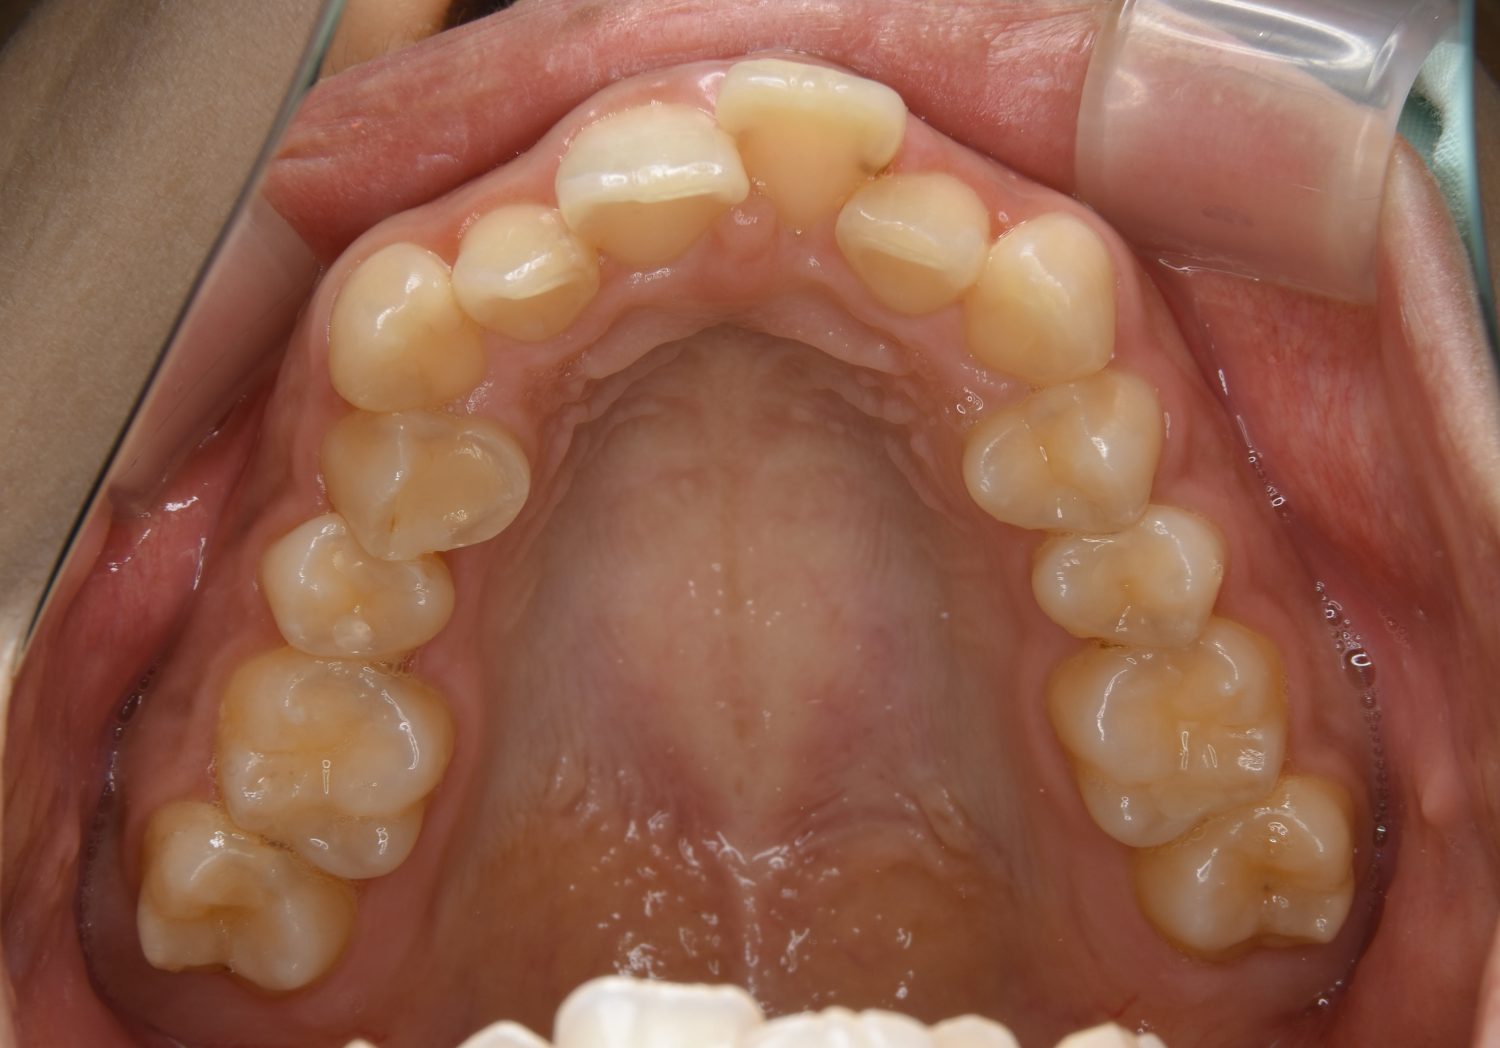

叢生の症例紹介①

Before

After

主訴

前歯のガタガタが気になる。

治療内容

上顎左側第一小臼歯を抜歯し、アライナー(インビザライン)にて治療を行いました。

治療費

1,150,000 円(税込)

治療期間

23ヶ月

通院回数

13回

想定されたリスク

※歯根吸収、歯肉退縮、歯髄壊死、顎関節症状

※アライナー(インビザライン)は日本の薬機法未承認の矯正装置であり、医薬品副作用被害救済制度の対象外となる場合があります。

丸山和宏先生

ピーススマイル矯正歯科

左上の側切歯が完全に内側に入り込んでいる状態でした。左上の第一小臼歯のみ抜歯を行い治療を行うことで機能面および審美面を改善しました。